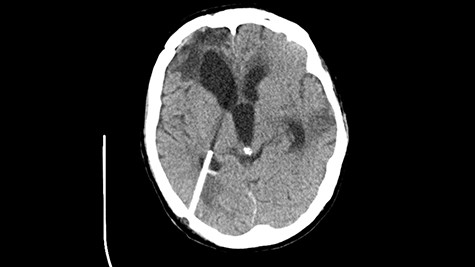

A 49-year-old patient presented after surgical treatment of nasal polyps, with headache and consciousness disorders (behavioral changes, drowsiness and allophenic orientation disorders). Computed tomography (CT) scan showed (Fig. 1) a presence of blood in fluid spaces, widening of the ventricular system (without active hydrocephalus features) and presence of air in the frontal horns of the lateral ventricles and features of cerebral edema. Due to the subarachnoid hemorrhage, an angio-CT and CT scan was performed, showing no vascular malformation. The patient's condition deteriorated with a drop in Glasgow Coma Scale (GCS) to 9, strongly expressed meningeal syndrome and a fever of > 38°C. In the performed cerebrospinal fluid examination a typical picture for bacterial infection, cultures negative. Treatment was implemented in accordance with the neuro-infections algorithm. Clinical and laboratory features of neuroinfections have withdrawn. The neurological condition of the patient improved to GCS 11. Control head CT (Fig. 2) showed enlargement of the ventricular system with cerebrospinal fluid transudation.

Head CT—state before VP shunt implantation. (Department of Neurosurgery own material).

After improvement of patient’s neurological status, a CT scan of the head revealed enlargement of the ventricular system with the features of cerebrospinal fluid transudation (Fig. 2), thus the patient has been qualified for a VP shunt implantation (Fig. 6).